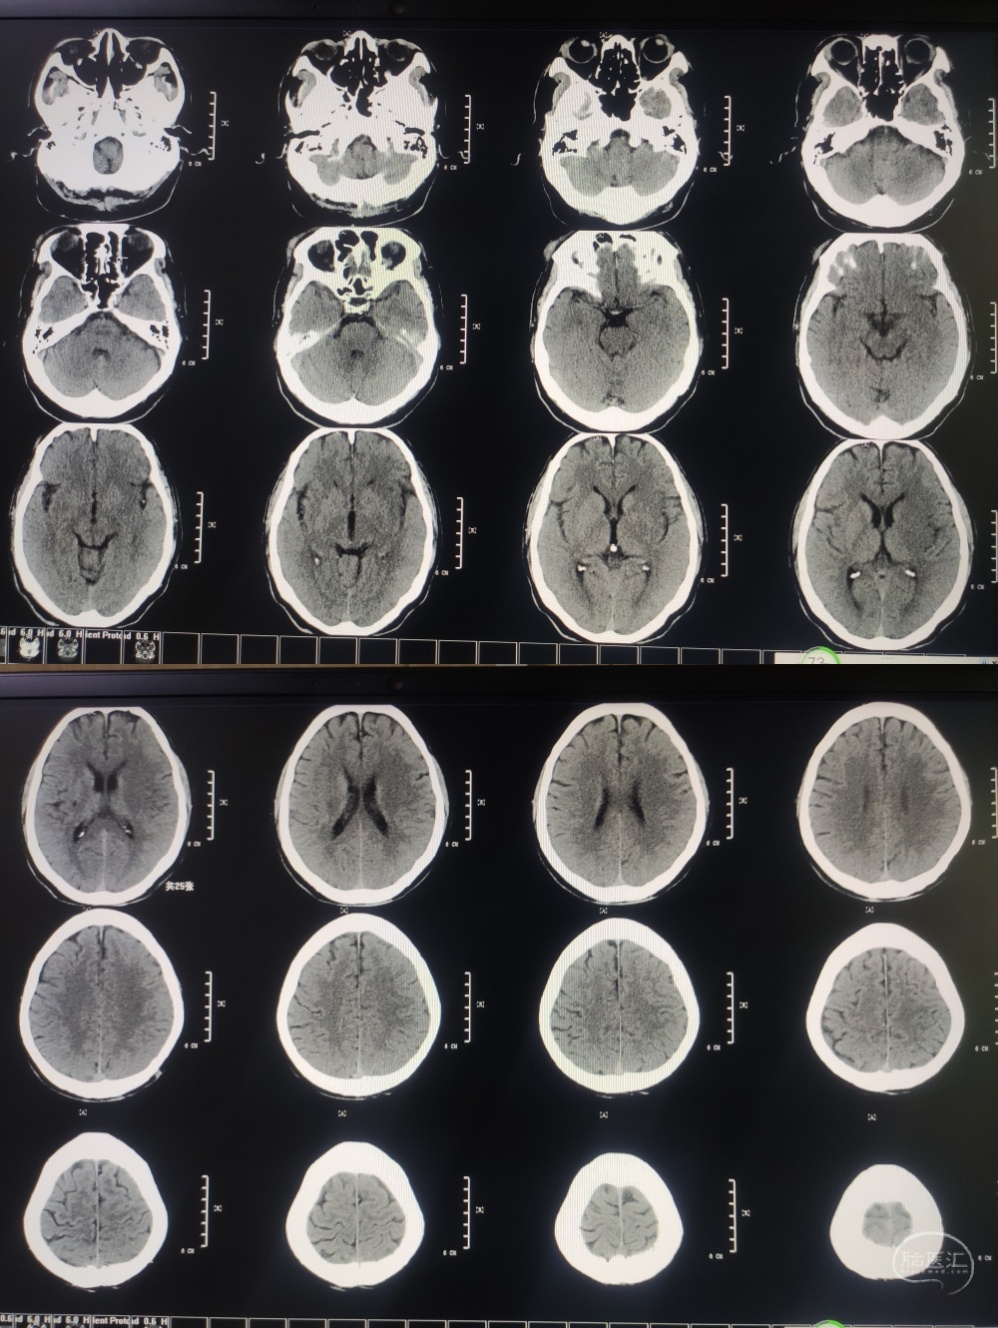

65岁男性,主诉:发现右侧肢体无力,言语不能3小时。NHISS评分:16分,CT-ASPECT评分:5分。

MRA提示:左侧颈内动脉末端及左侧大脑中动脉未见显影。DWI提示左侧大脑中动脉供血区高信号。DWI-Aspect评分:4分。醒后卒中,DWI信号不高,考虑存在大体积缺血半暗带,急诊血管内治疗。

3.术后血管通畅,术前Aspect评分低,最怕高灌注,所以到重症不醒麻醉,脱水,控制血压,降颅内压及对症支持治疗。